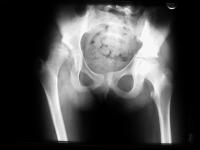

Abbildung 5: Coxa valga subluxans rechts bei spastischer Hemiparese rechts. Der Hüftkopf bereits deformiert, zur Hälfte aus der hochgradig dysplastischen Pfanne luxiert, deutliche Adduktionsfehlstellung durch den Adduktorenspasmus.